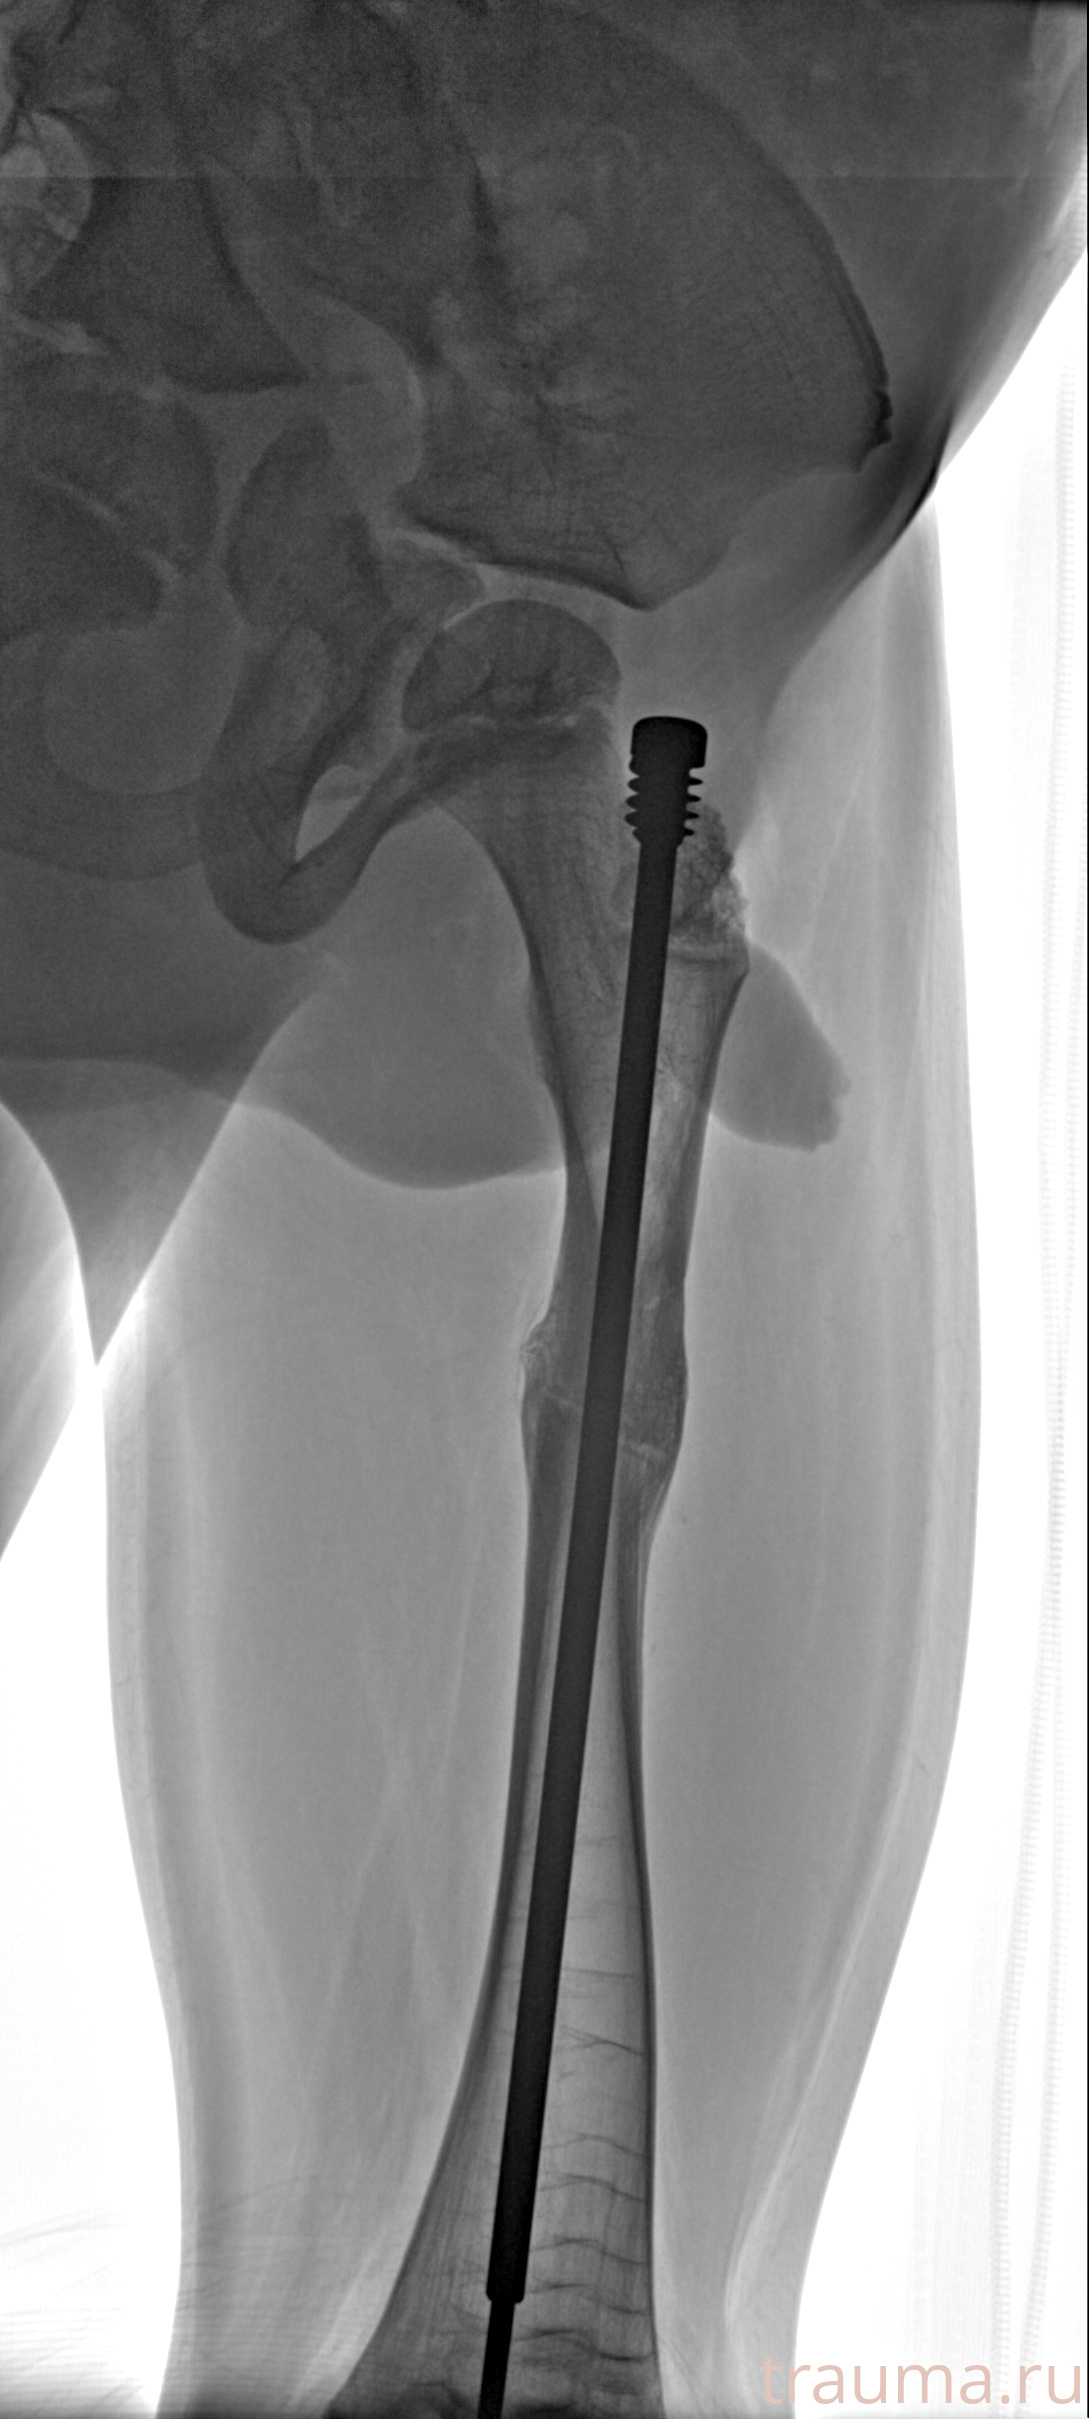

Рентгенограммы

Рентген на дому: по вашему адресу приезжает врач-рентгенолог, травматолог-ортопед с мобильным рентгеновским аппаратом, проводит диагностику травмы или заболевания, делает необходимые рентгенограммы, дает рекомендации по дальнейшему лечению. Получить качественные снимки в домашних условиях возможно благодаря уникальной методике, разработанной МосРентген Центром для института  Склифосовского